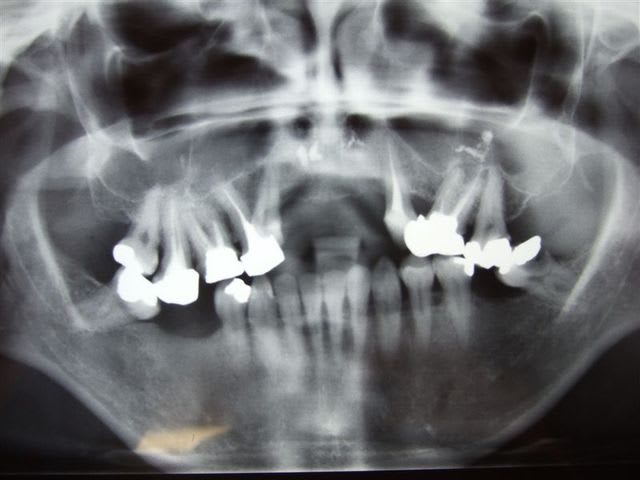

- patiente qui se plaint de douleurs mol inf et pb articulaires : cf empreintes et pano

- extraction 47/37 avec entre temps foyer infectieux sur 26 qui se manifeste : dépose cc et tentative RTE : très mauvais pronostic car résine phénoplaste qui au premier abord ne se laisse pas faire.